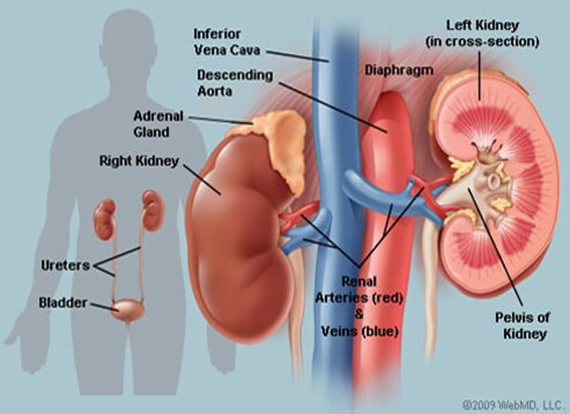

– Chronic renal failure

– Kidney disease